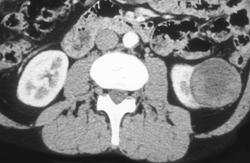

Oncocytoma